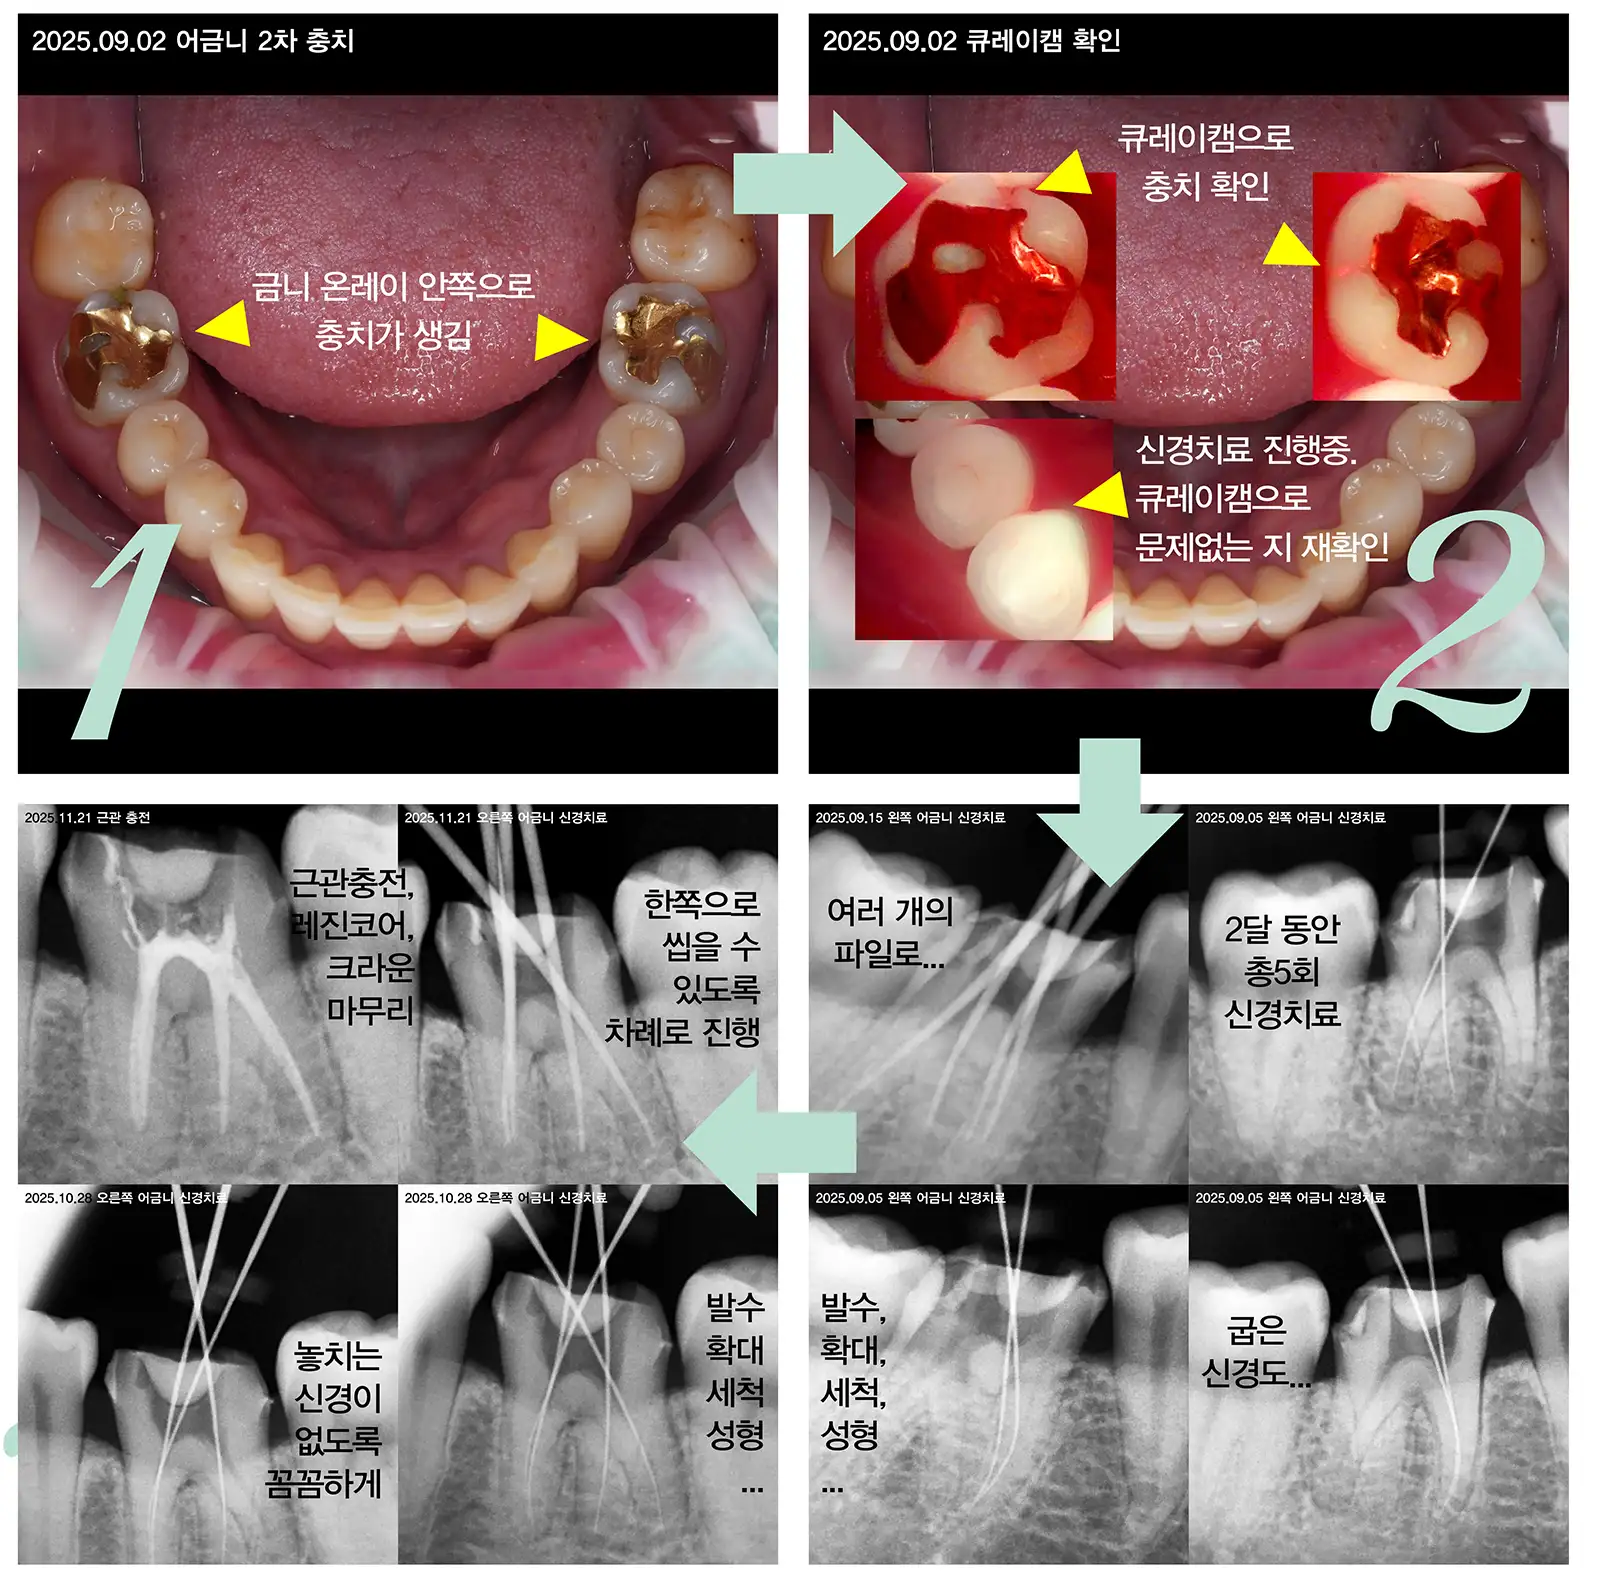

총5회 신경치료로 치아를 살린 사례

치수염으로 더 이상 회복이 불가능한 근관 속 신경을 제거하고 밀봉하는 치료입니다. 감염된 신경과 혈관 조직을 깨끗이 긁어내고, 가느다란 기구와 소독액을 이용해 관 내부를 깨끗하게 청소한후 텅 빈 근관에 인공 재료를 채워 넣어 세균이 다시 침투하지 못하게 밀봉합니다.

신경치료 과정

신경 치료는 건강보험이 적용되어 비교적 저렴합니다. 내원 횟수, 치아의 위치, 파일 사용량에 따라서 가격이 달라집니다.

근관 충전과 코어

신경 치료 후 보철물을 올리기에는 구조적으로 취약한 경우에 치아를 보강하기 위해서 여러가지 방법을 사용합니다.

• +MTA 근관충전(C형근관): C형 근관은 신경관들이 알파벳 C자 모양으로 서로 연결되어 있거나 복잡하게 얽혀 있는 형태를 말합니다. MTA는 습한 환경에서도 잘 굳는 생체 친화적인 특수 시멘트입니다. 근관에 MTA를 충전하면 미세한 틈까지 흘러 들어가 완벽하게 메워주고 항균 작용이 있고 주변 조직의 재생을 돕는 성질이 있어 예후가 훨씬 좋습니다.

• +레진 코어: 신경 치료를 위해 치아 가운데에 구멍을 내고 충치를 제거하면 치아 내부가 텅 비게 됩니다. 이 텅 빈 공간을 레진으로 만든 코어로 채워 기둥의 몸통을 만듭니다. 자기 치아 벽이 어느 정도 튼튼하게 남아 있을 때 사용합니다.

복잡한 신경관은 MTA로 확실히 밀봉하는 것이 재발 방지의 핵심이며, 이후 남아 있는 치아의 양에 따라 레진 코어만 할지, 혹은 뿌리에 기둥을 세우는 포스트 코어까지 할지를 결정하게 됩니다. 이 과정들이 꼼꼼하게 이루어져야만 먼훗날 크라운이 빠지거나 치아 뿌리가 부러지는 불상사를 막을 수 있습니다.